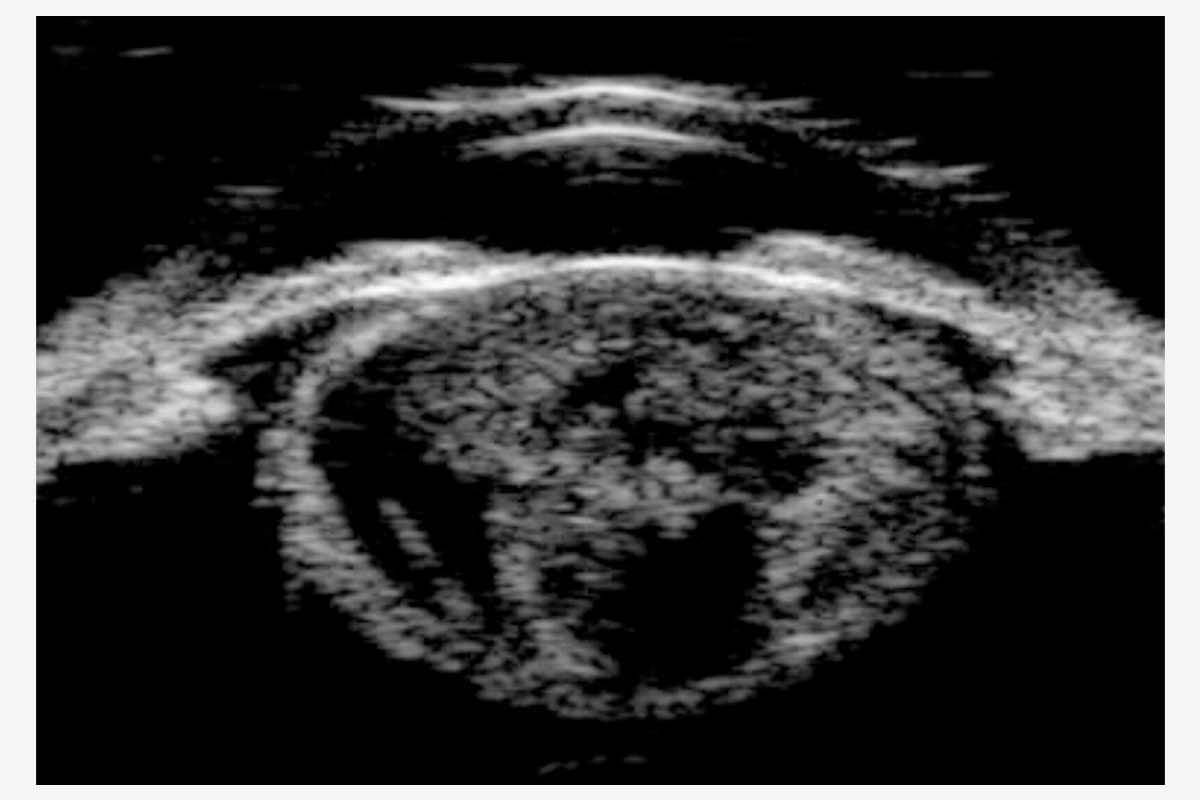

A la exploración, destacaba una catarata hipermadura, PIO de 9 mmHg y daño glaucomatoso avanzado (copa/disco 0.9). La estrategia quirúrgica se definió mediante la microscopia especular y la UBM: un RCE crítico de 997 células/mm² (Figura 3) y un cristalino de gran diámetro anteroposterior con lens vault aumentado (Figura 4).

Figura 4. UBM mostrando catarata con aumento del diámetro AP y del lens vault